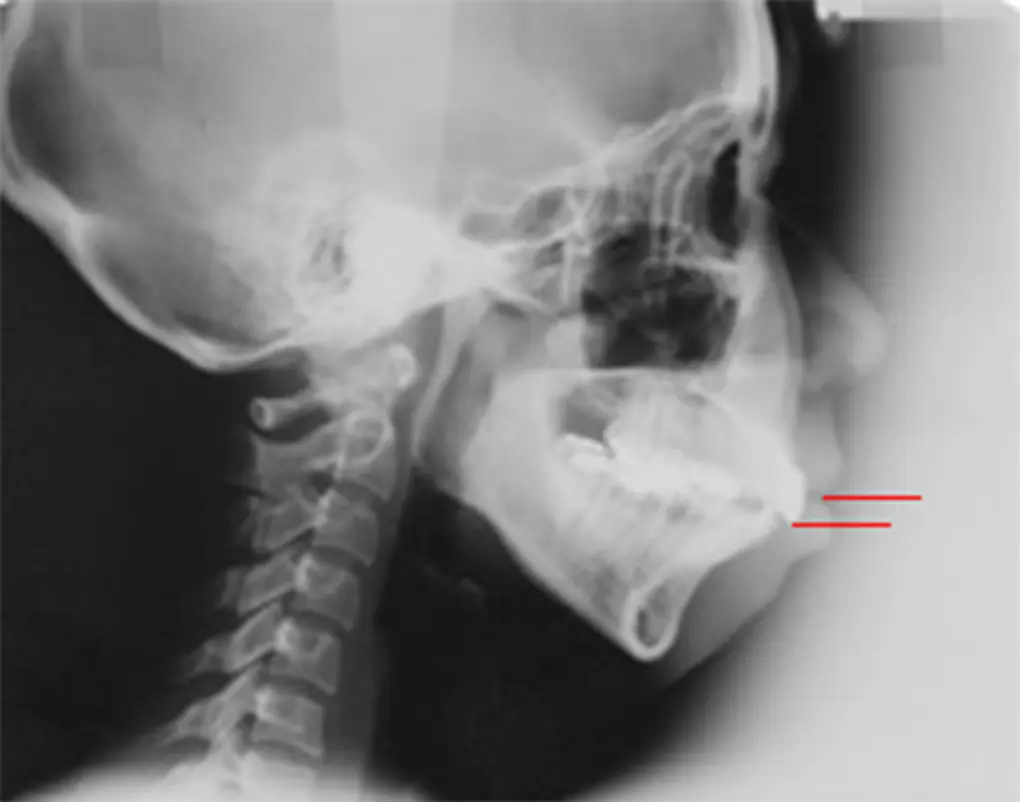

歯列全体を上方へ引き上げることで、改善を図ります。

今までは外科手術が必要な症例でしたが、歯科矯正用アンカースクリューを使うことで、多くの症例が外科手術せずに改善が見込めます。

| 患者さまの年齢・性別 | 30代・男性 |

|---|---|

| 治療期間 | 2年2ヵ月 |

| 治療費(税込) | 1,567,500円 |

| 主訴 | ガミースマイルが気になる。 |

| 診断名・主な症状 | 過蓋咬合 |

| 治療に用いた主な装置 | 舌側矯正装置、歯科矯正用アンカースクリュー |

| 治療内容 |

歯科矯正用アンカースクリューにより上顎前歯を上方と後方に移動させ、ガミースマイルと上顎前突の改善を行ないました。 |

| 抜歯部位 | 非抜歯 |